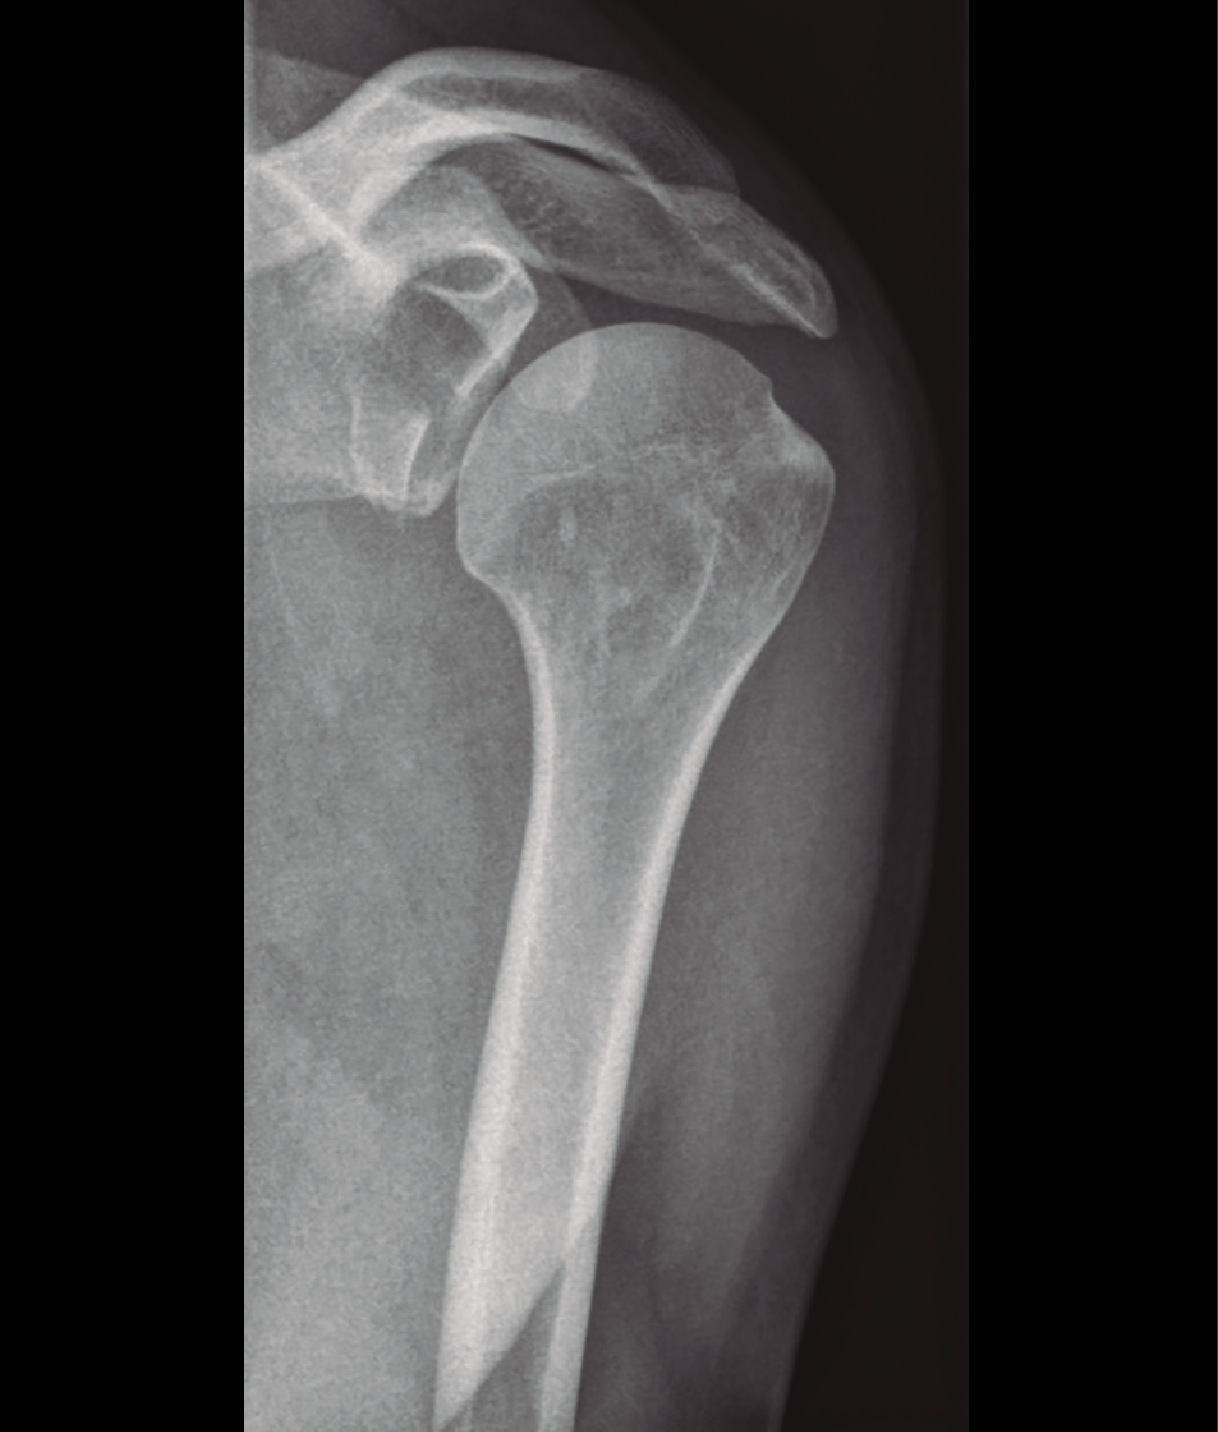

Figura 3. Radiografía simple de fractura glenoidea.

Existen distintos tipos de fracturas escapulares. En ocasiones, tras una fractura glenoidea (35%) (Figura 3), pueden producirse fracturas de coracoides (7%) (Figura 4) y también pueden ocurrir fracturas escapulares indirectas por caídas con la mano extendida(1,3,5).